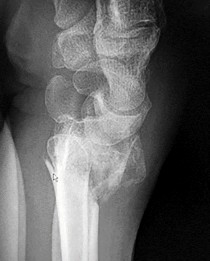

A 22-year-old male falls onto an outstretched hand and sustains a displaced fracture through the proximal pole of the scaphoid. Avascular necrosis of the proximal pole is highly likely due to the disruption of its primary vascular supply. Which vessel provides this critical retrograde perfusion?

Explanation

The primary blood supply to the scaphoid is from the dorsal carpal branch of the radial artery, which enters the dorsal ridge of the scaphoid at the waist and courses proximally. This retrograde blood flow makes proximal pole fractures highly susceptible to avascular necrosis and nonunion. The superficial palmar branch provides a minor supply (about 20%) to the distal pole.